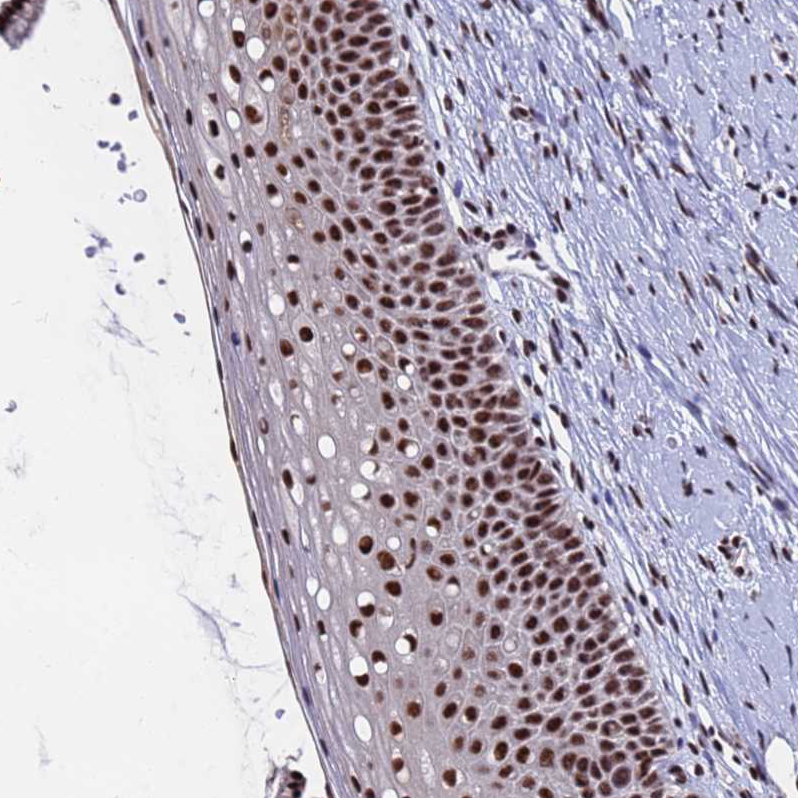

Immunohistochemical staining of human testis shows strong nuclear positivity in cells in seminiferous ducts.